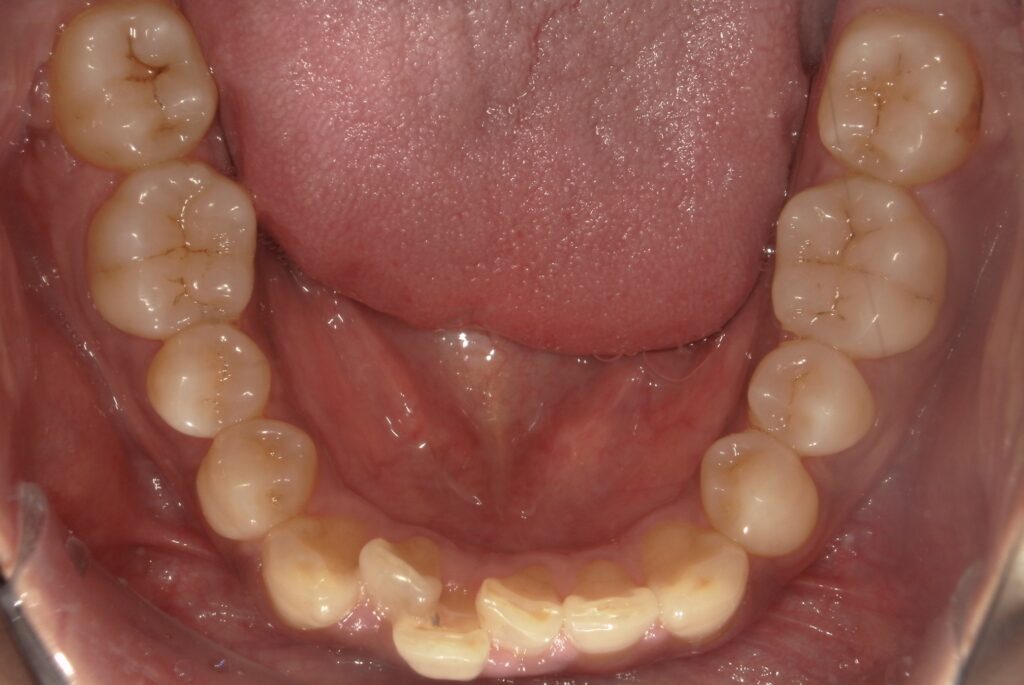

Before

After

ガタつき / かみ合わせ

- 30代男性

- 主訴:前歯のガタつきと噛み合わせを良くしたい

- 矯正方法:インビザラインの非抜歯矯正

- 治療期間:9ヶ月

- 治療費:710,000円

- その他ご要望:治療期間を早くしたい、マウスピースを早く受け取りたい。

- 詳しくはこちら

ご相談内容 前歯のガタつきと噛み合わせが気になると30代男性からのご相談 現状と治療方針 前歯のガタつきが見られます。また、下の前歯を上の前歯が大きく被さっているため、下の前歯が見えない過蓋咬合(ディープバイト)が見られます。奥歯をさらに後ろに下げる遠心移動と、歯と歯の間にわずかなスペースを作る方法で矯正を行いました。 治療結果 ガタつきと噛み合わせを9ヶ月で改善できました。 振り返り 今回の患者様は他院で不信感があり、ご紹介という形でセカンドピニオンを受けるために当院にお越しいただきました。お仕事が多忙のため治療期間を早くすることが一番重要なご要望でしたが、全体矯正にも関わらず9ヶ月で矯正を終えることができたことに大変喜んでいただけました。 リスク・副作用 マウスピースの装着時間を守っていただけないと矯正治療に時間がかかり、場合によっては治療がうまく進まない可能性があります。